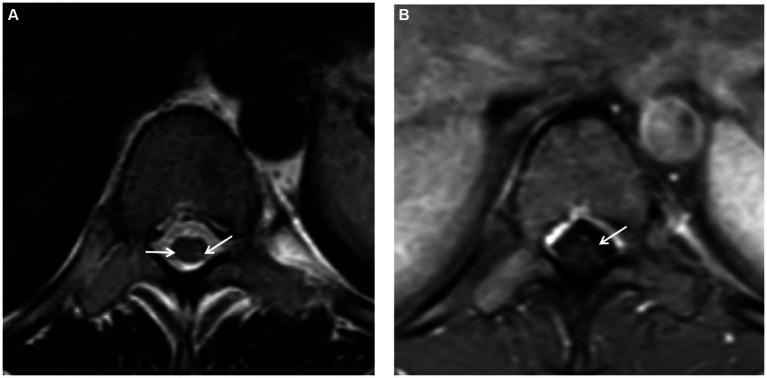

The abuse of nitrous oxide (NO) poses a substantial public health challenge. In many countries, including China, regulations governing the utilization and accessibility to NO remain ambiguous, particularly within the food industry. Here, we report a case of a 21-year-old female who presented with symptoms of subacute combined degeneration (SCD) of the spinal cord due to NO abuse. The patient exhibited bilateral lower limb numbness and weakness, low serum vitamin B12 levels with elevated homocysteine levels, and lumbar spine magnetic resonance imaging (MRI) revealed abnormal signals of the spinal cord. Following cessation of NO and comprehensive therapy including methylcobalamin and nerve growth factor, the symptoms significantly improved. A follow-up examination 3 months later showed good progress in gait stability. At a 5-year follow-up, the patient's previous clinical symptoms had completely disappeared, and her quality of life had returned to normal. This case underscores the urgency of raising awareness and prevention of NO abuse, emphasizing the importance of timely diagnosis and comprehensive treatment for patient recovery. Clear formulation and enforcement of relevant regulatory measures are equally crucial in reducing instances of abuse.

一氧化二氮(NO)的滥用对公众健康构成了重大挑战。在包括中国在内的许多国家,关于NO使用和获取的规定仍然不明确,尤其是在食品行业。在此,我们报告一例21岁女性因滥用NO出现脊髓亚急性联合变性(SCD)症状的病例。患者表现为双侧下肢麻木和无力,血清维生素B12水平低且同型半胱氨酸水平升高,腰椎磁共振成像(MRI)显示脊髓信号异常。在停止使用NO并进行包括甲钴胺和神经生长因子在内的综合治疗后,症状明显改善。3个月后的随访检查显示步态稳定性有良好进展。在5年的随访中,患者先前的临床症状完全消失,生活质量恢复正常。该病例强调了提高对NO滥用的认识和预防的紧迫性,强调了及时诊断和综合治疗对患者康复的重要性。明确制定和执行相关监管措施对于减少滥用情况同样至关重要。